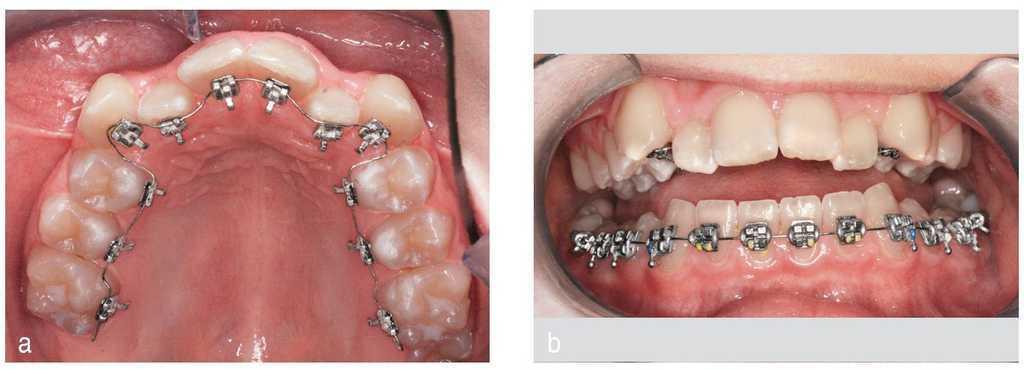

En este caso se utilizó también un sistema de brackets arco de canto labial convencional en el maxilar combinado con los mismos brackets linguales de técnica bidimensional en la mandíbula2 (fig. 20). Hicieron falta sólo dos arcos por arcada para la parte activa del tratamiento8 (fig. 21).

Figura 20. Aparato arco de canto labial en el maxilar, aparato lingual de técnica bidimensional en la mandíbula.

Figura 21. Segundo y último arco.